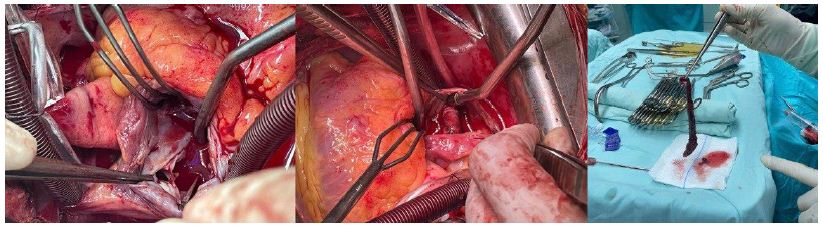

Given the echocardiographic findings, the patient was prepared for the surgical excision of the right atrial mass. Intraoperatively, it was discovered that the cylindrical mass in the RA extended into the LA through a PFO (see Figure 1). The interatrial septum was subsequently opened, allowing for the complete excision of the mass. The excised mass was then sent for histopathological examination, which confirmed the diagnosis of a thrombus.

Figure 1: Demonstrates Intraoperative Views, The left image presents a close-up of the heart, highlighting the attachment point of the mass. The center image illustrates the cylindrical mass within the heart chambers. The right image depicts the excised long, cylindrical mass.